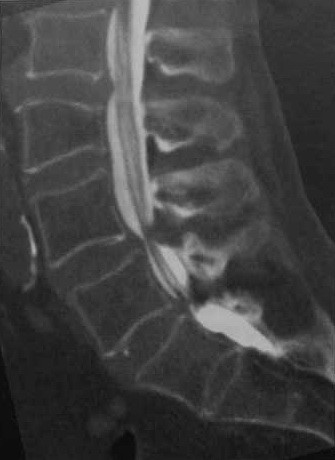

Женщина 69 лет с длительным болевым синдромом в поясничной области и типичной позвоночной хромотой. Постмиелографическая КТ (сагиттальная рекон¬струкция). Стеноз спинномозгового канала высокой степени на уровне L4-L5 и L5-S1, вызванный протрузией межпозвонкового диска, артритом суставных поверхностей и гипертрофией желтой связки.

а, b Мужчина 80 лет с абсолютным стенозом спинномозгового канала на уровне L3-L4 и L4-L5:

a) Сагиттальное Т2-взвешенное изображение. Стеноз спинномозгового канала в связи с концентрической протрузией диска, спондилоартритом и гипертрофией желтой связки. b) Сагиттальное изображение последовательности конструктивного вмешательства в стабильном состоянии (055) с толщиной срезов 1 мм. Волокна конского хвоста, расположенные краниальнее места стеноза, имеют типичное удлиненное и волнистое изображение.